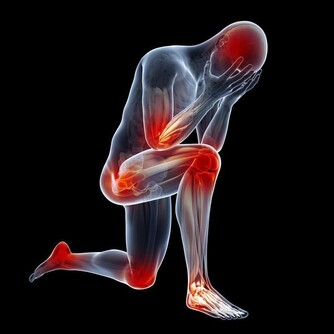

白天咳得少,經常在夜間兩三點時咳醒哭鬧,而且鼻子喘氣聲音特別大,睡眠中總是哼哼唧唧不安穩,可能是肝火旺盛,要想辦法降肝火。也有可能是上呼吸道阻塞,建議帶寶寶檢查耳鼻咽喉。

吹風著涼後咳嗽,聲音通常是沉重的,頻率較高,伴有清水鼻涕,少痰,睡覺時呼吸聲較重,孩子總說鼻子難受。

如果孩子不僅咳嗽還有發燒、咽痛、嗓子啞,說明是被風熱侵襲肺部,咳嗽聲比較響,比較急促。

不僅咳還有點喘,有“吼”聲,暗示肺部問題有點嚴重,建議找醫生處理,不要亂吃止咳藥。